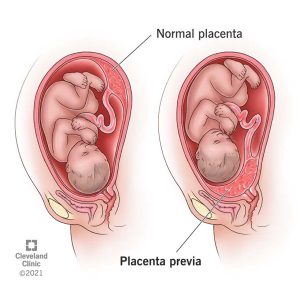

Ni urutiriro rw’inda rufasha umwana kubona amaraso, intungamubiri, n’umwuka. Placenta ikunze kwifata ku rukuta rw’inyababyeyi (uterine wall), cyane cyane mu gice cyo hejuru cy’inyababyeyi (fundus) cyangwa inyuma (posterior wall). Aha ni ho haba amaraso menshi, bikayiha ubushobozi bwo guha umwana ibiryo n’umwuka.

Kuba placenta ikunze kwifata hejuru cyangwa inyuma bituma inzira y’umwana (inkondo y’umura) idahagarikwa, bityo kubyara bikagenda neza.

2- Placenta itameze neza:Placenta iba ishobora kuba ifashe nabi kuri nyababyeyi cyangwa ikaba iri hasi cyane (placenta previa), ishobora kubuza inzira y’umwana cyangwa gutera kuva. Iyo itandukanye hakiri kare (placental abruption), bishobora gushyira ubuzima mu kaga. Ubusanzwe placenta isohoka…

– Placenta ifashe nabi cyangwa ikitandukanya kare: Iyo placenta iri hasi cyane (placenta previa) cyangwa ikitandukanya hakiri kare (placental abruption), umwana ashobora kubura umwuka.

4. Placenta previa cyangwa abruption

– Placenta previa: Placenta iri hasi cyaneyitambikaa inzira y’umwana, bikaba bigoye kumusohora.

– Placental abruption: Igihe Placenta yitandukanya hakiri kare, bigatera kuva cyane no kubuza umwana umwuka. Ibi bibazo byombi bishobora gushyira ubuzima bw’umubyeyi n’umwana mu kaga.